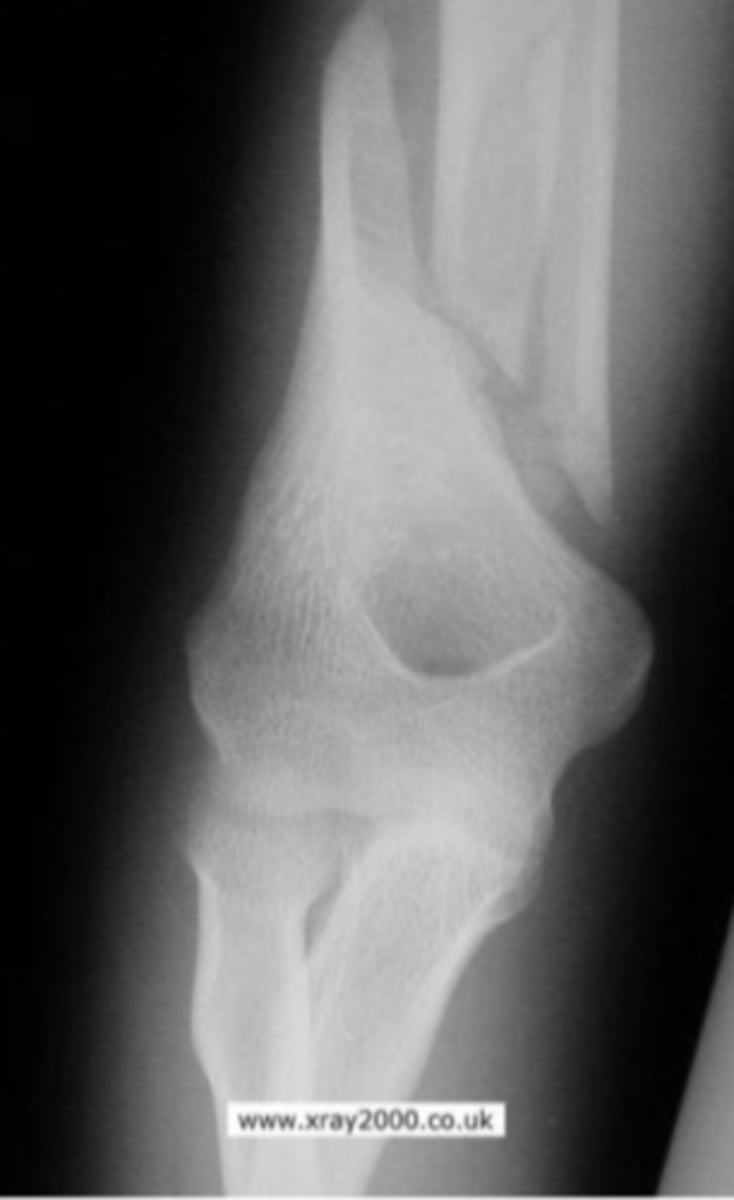

Medial epicondyle avulsion fracture

What is the issue?